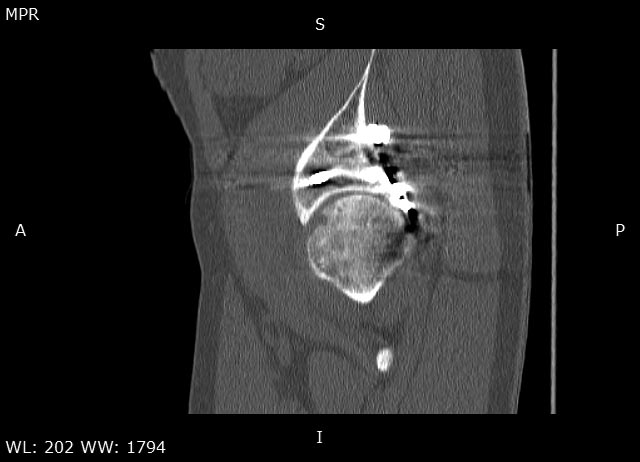

Мужчина 32 года, беспокоят боли в левом тазобедренном суставе, преимущественно в задних отделах при отведении ноги, иногда боли в паху с иррадиацией по внутренней поверхности до колена.

Травма в 2015 году. Водитель, попал в ДТП. Первично повреждение печени, перелом локтевой кости слева. Перелом задней колонный и задней стены левой вертлужной впадины. По экстренным показаниям выполнялась лапаротомия. Синтез задней колонны и задней стены через 13 дней через доступ Кохера-Лангенбека. Гладкий послеоперационный период. Выписан на амбулаторное лечение через 15 дней после операции. После выписки к нам не обращался, так как является жителем другого региона. Обратился через 2,5 года с жалобами на боли в области левого тазобедренного сустава.

На РКТ таза - перелом сросся. Отмечается кисты в области верхнего полюса головки бедра. Пластина фиксирующая задний край соприкасается с задними отделами головки бедра (видимо произошел частичный лизис костного края).

У пациента посттравматический коксартроз 2ст. Учитывая невыраженный болевой синдром лучше ограничиться удалением металлоконструкции. Головка не деформирована кисты относительно небольшого размера - продолжить консервативное лечение с ограничением нагрузок занятий спортом. Упражнения для сохранения мышц и объема движений, бассейн.